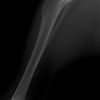

ミニチュアダックスフンド 9歳 未去勢♂

突然の非負重性の右後肢跛行を主訴に来院されました。触診上、右膝の伸展痛が認められ、整形外科学的検査において右膝の内外側の膝蓋骨脱臼(Grade Ⅱ)、脛骨圧迫テストで陽性が認められました。神経学的検査において特に異常は認められませんでした。レントゲン検査において、関節液の貯留所見や脛骨の前方変位の所見は認められませんでいた。

関節穿刺を行い、好中球はなく、少数のマクロファージや滑膜細胞が認められるました。膝蓋骨脱臼および前十字靭帯断裂による退行性の関節炎を疑い、関節鏡検査を実施いたしました。関節鏡検査では、重度の滑膜炎および前十字靭帯の完全断裂が認められました。内外側とも半月板に損傷は認められませんでした。

写真の膝関節の垂直線を綿棒の木柄が表しており、遠位の脛骨粗面との位置関係が平行ではありません。